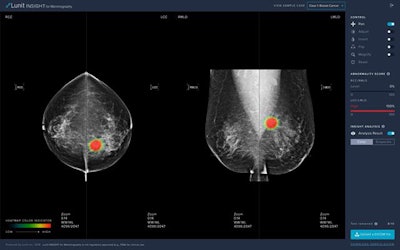

Lunit Insight MMG analyzes mammography images to provide information on the location of suspicious lesions and generate an abnormality score. Lunit intends for the software to improve mammography's effectiveness and reduce the number of unnecessary breast biopsies.

The Lunit Insight MMG artificial intelligence software. Image courtesy of Lunit.Lunit Insight MMG received CE certification on 26 May, paving the way for its sale in the United Kingdom and European Union. Lunit first introduced the AI software at the 2018 Radiological Society of North America (RSNA) annual meeting. It was also the subject of a February study in Lancet Digital Health that found the performance of radiologists improved after the addition of AI.